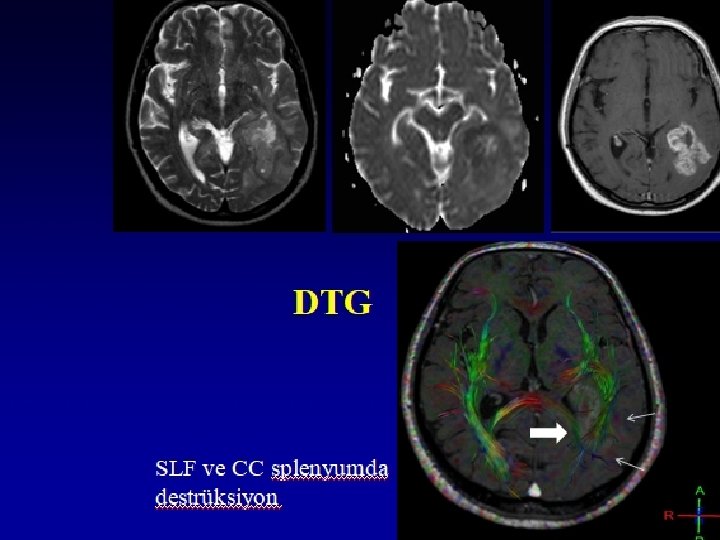

MR TRAKTOGRAFİ • Difüzyon Tensör Görüntüleme (DTG) ile elde edilen verilerin önemli bir özelliği dokulardaki difüzyonun hangi yönde daha fazla olduğunun anlaşılabilmesidir. • Böylece ölçüm yapılan alandaki beyaz cevher yolaklarının yönü hakkında bilgi alınabilir. • Beyaz cevher yolaklarına ait traktografi görüntüleri beyin görüntüleri üzerinde 3 boyutlu olarak gösterilebilir.

DİFFÜZYON TRAKTOGRAFİ (Beyaz cevher fiber traktlarının 3 D görüntüde gösterilmesi)